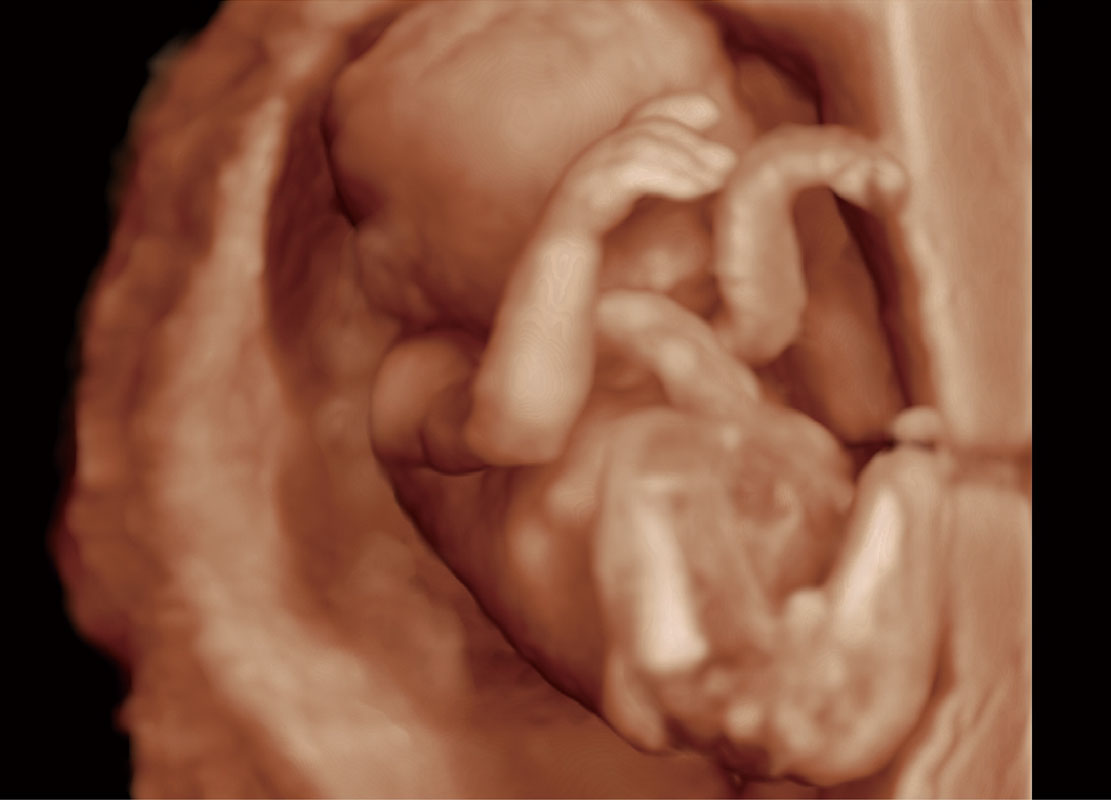

中晚孕筛查

P60提供简单易学易用的高端诊断工具,为您中晚孕筛查提供快速清晰的解剖信息。

S-Fetus能够助您在实时扫查过程中自动识别标准切面、自动测量并录入报告。一个按键,即可快速、高效地获取胎儿生理指标,简化您的产科检查操作。